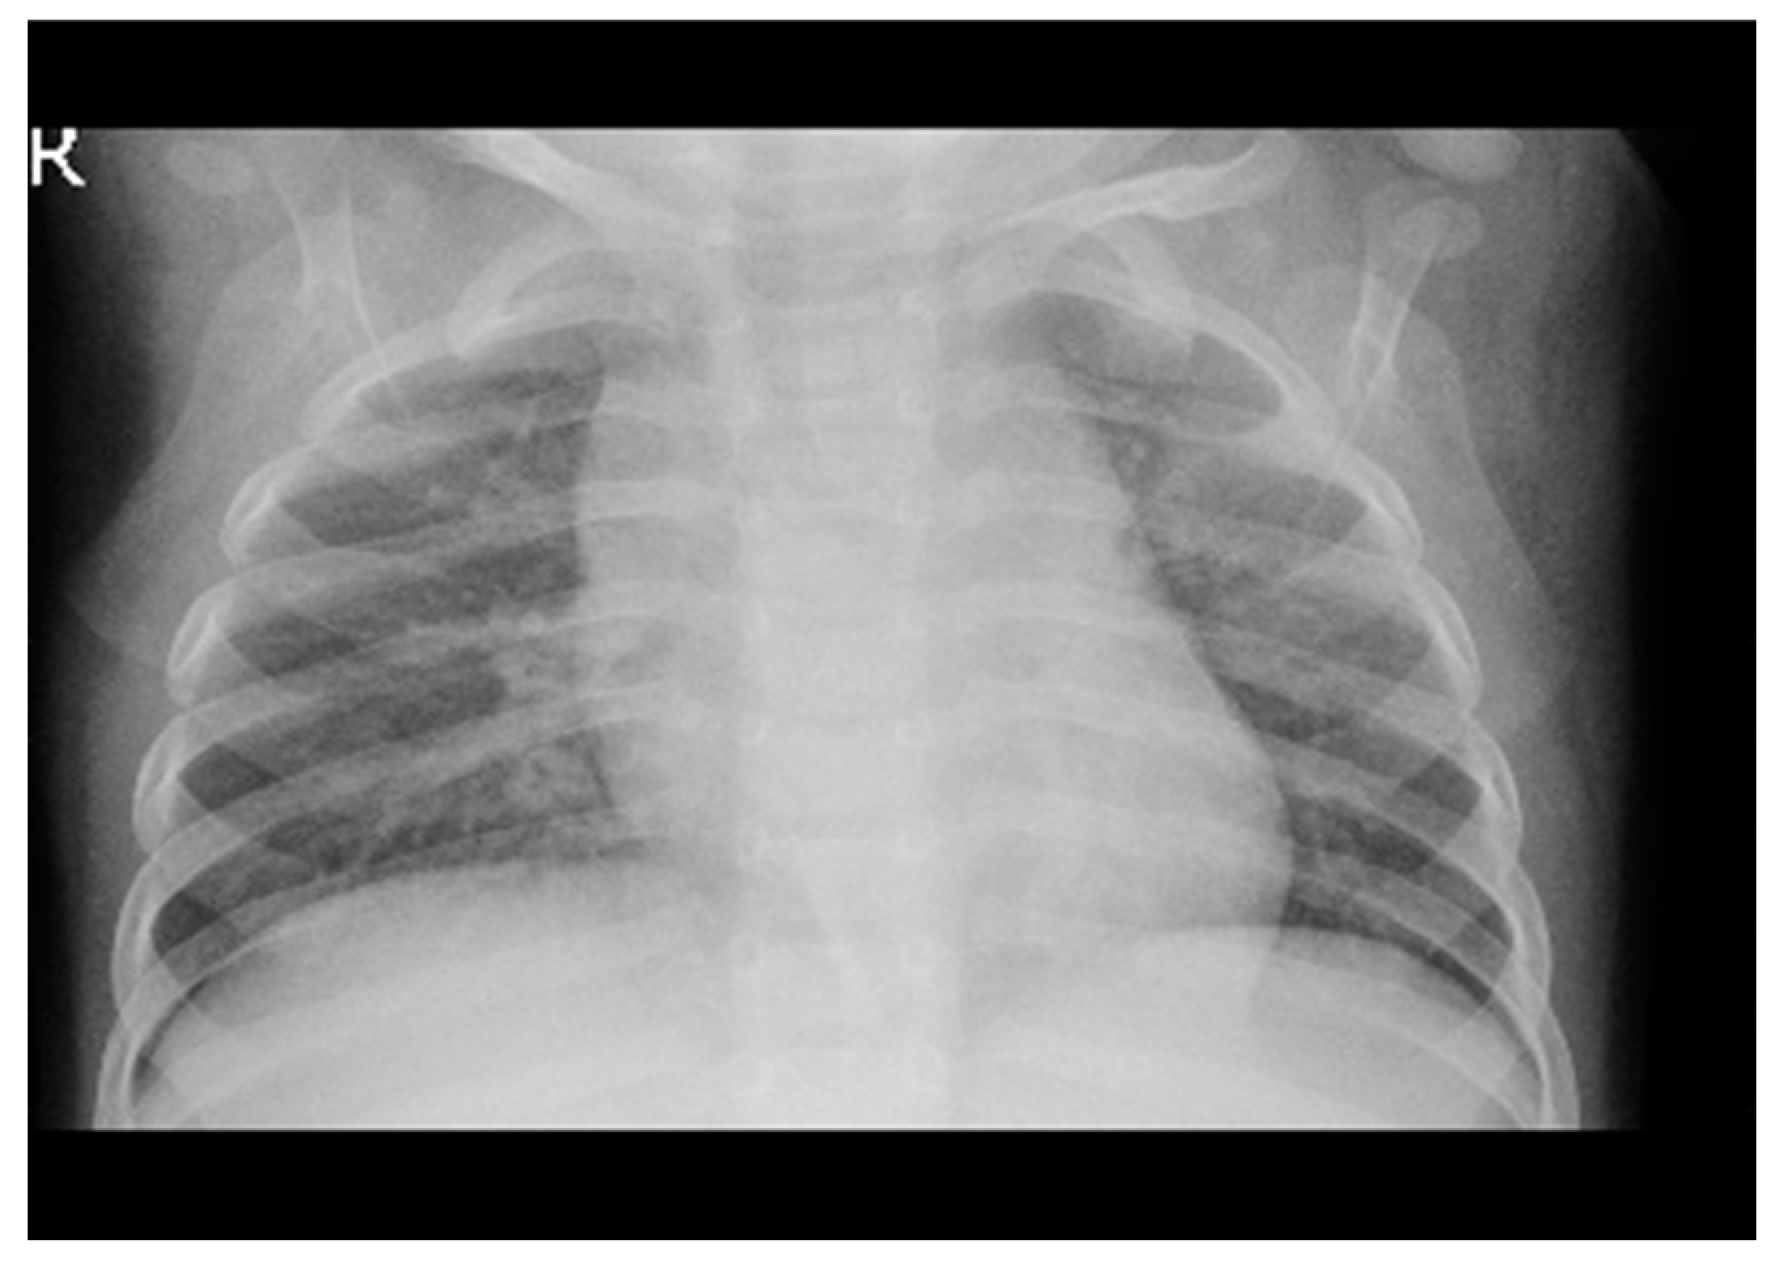

The model utilizes a compact dataset containing 5863 chest X-ray images from distinct patients. It classifies images with pneumonia as one of the annotated pathologies as positive examples, while marking all other images as negative examples. The dataset is partitioned into training, testing, and validation sets for the pneumonia detection task, ensuring no patient overlap between them. Prior to feeding the images into the network, they undergo downscaling to 224x224 dimensions.

In the model testing phase, a specific test set is employed, comprising 234 normal and 390 pneumonia patient frontal chest X-rays. Radiologists, devoid of access to patient information or knowledge of disease prevalence, label the images using a standardized data entry program.